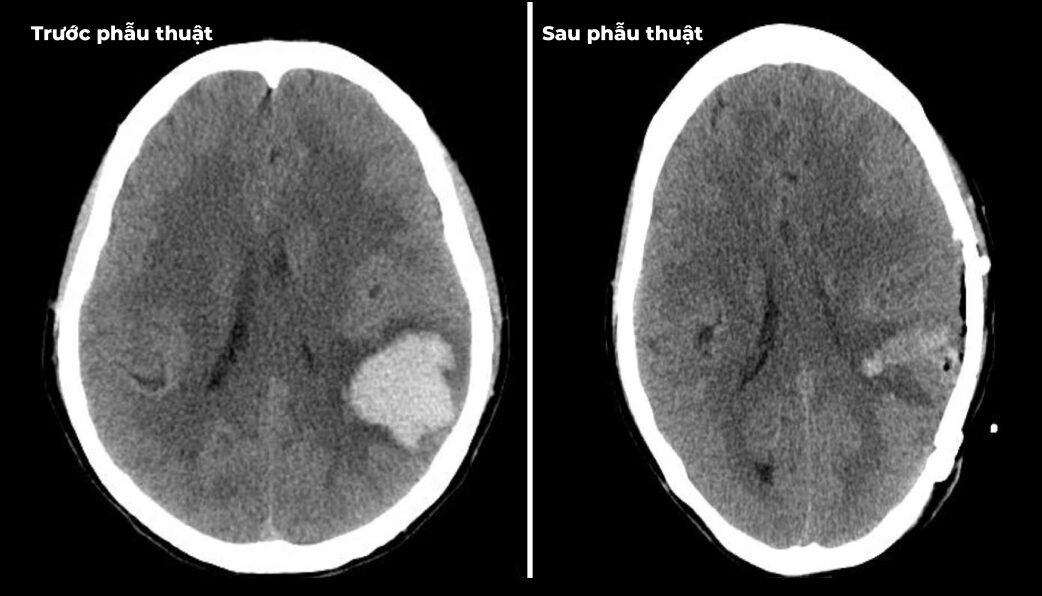

Thông tin từ Bệnh viện Đa khoa Hùng Vương cho biết, khi vào viện, cả hai bệnh nhân đều trong tình trạng nguy kịch, rối loạn ý thức, huyết áp cao kịch ngưỡng. Ngay lập tức, các bác sĩ đã khẩn trương cấp cứu, tiến hành phẫu thuật để kiểm soát tình trạng chảy máu não và giảm áp lực nội sọ. Nhờ can thiệp kịp thời, hiện tại các bệnh nhân đã qua cơn nguy hiểm. Tuy nhiên, di chứng để lại vẫn rất nặng nề, ảnh hưởng nghiêm trọng đến sức khỏe và chất lượng cuộc sống. Đây là hồi chuông cảnh báo về sự nguy hiểm của bệnh tăng huyết áp, đặc biệt ở người trẻ tuổi – nhóm đối tượng thường chủ quan, không kiểm tra huyết áp định kỳ.

Bác sĩ đã khẩn trương cấp cứu, tiến hành phẫu thuật để kiểm soát tình trạng chảy máu não và giảm áp lực nội sọ